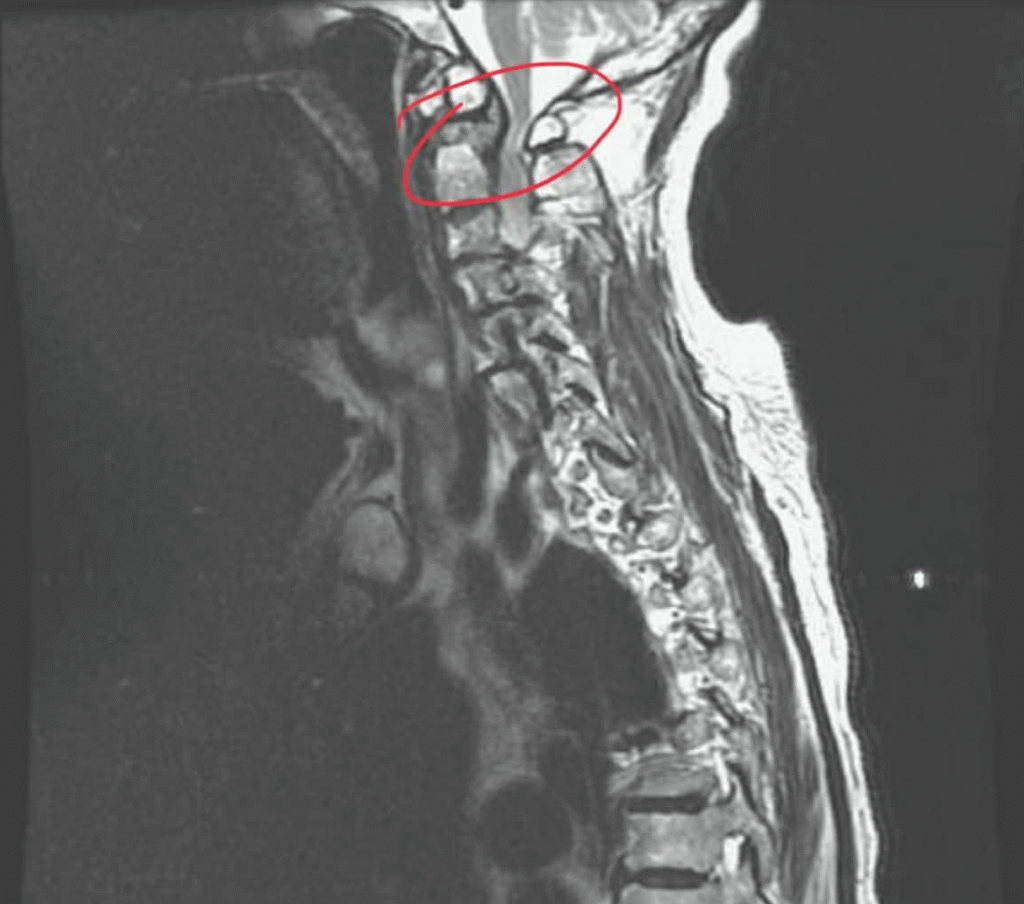

影像檢查診斷 C1 椎管狹窄,X光片初步懷疑後可以安排:

- 核磁共振MRI:觀察脊髓是否受壓及是否出現訊號變化

- 電腦斷層CT:評估骨頭結構與椎管形態

臨床上常使用「脊髓可用空間(SAC)」來判斷狹窄程度。一般而言,當空間過度縮小時,出現神經症狀的風險會顯著提高。